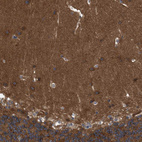

Immunohistochemical staining of human cerebral cortex shows strong cytoplasmic positivity in neuropil and neurons.